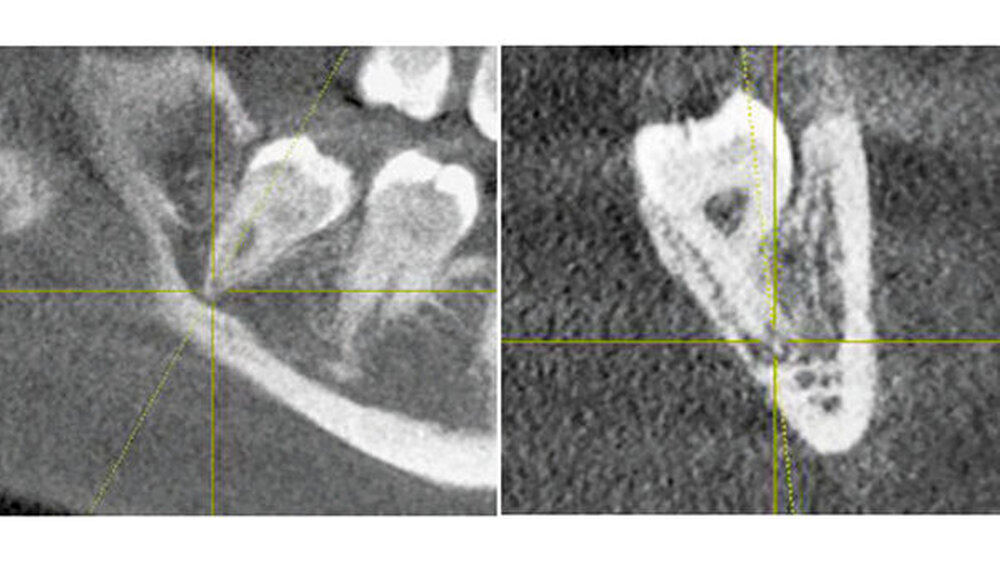

Bei der 27-jährigen, gesunden Patientin, kam es zu rezidivierender Perikoronitis des teilretinierten Zahns 48 (Abb. 1a). Primär wurde eine OPT-Aufnahme zur Operationsplanung erstellt (Abb. 1b). Dabei zeigte sich eine komplette Überlagerung der Zahnwurzel über den C. mandibulae. Zur weiteren Abklärung der Lagebeziehung wurde eine DVT-Aufnahme erstellt (Abb. 1c). Eine linguale Lage des C. mandibulae zur Zahnwurzel konnte festgestellt werden. Eine knöcherne Begrenzung des C. mandibulae zur Zahnwurzel fehlte.

Aufgrund des hohen intraoperativen Läsionsrisikos für den N. alveolaris inferior wurde eine Koronektomie geplant; die Patientin willigte nach eingehender Aufklärung ein. Präoperativ spülte sie mit 0,2 Prozent Chlorhexidin-Mundspülung (Curasept ADS® 220, Curaden AG, Kriens, Schweiz). Eine Leitungsanästhesie des N. alveolaris inferior sowie eine Infiltrationsanästhesie bukkal wurden durchgeführt (Ultracain ds forte, Sanofi-Aventis AG, Vernier, Schweiz).